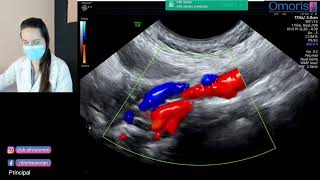

Web• Estará apto a realizar os exames básicos de ultrassonografia vascular: carótidas e vertebrais, arterial de membros inferiores e venoso de membros inferiores; • Conhecerá. WebQual a indicação para o exame de ultrassom doppler de carótidas e vertebrais? O exame ecodoppler de carótidas e vertebrais é indicado pelo médico para pessoas que. WebA Ecografia de Carótidas e Vertebrais com Doppler analisa as carótidas, que são artérias que passam pela região do pescoço, originadas na curvatura torácica da aorta e. WebO procedimento Doppler colorido de vasos cervicais arteriais bilateral (carótidas e vertebrais) faz parte da tabela Terminologia de procedimentos e eventos em saúde da. WebÉ um exame complementar de diagnóstico que utiliza... Doppler de Carótidas e Vertebrais? É um exame complementar de diagnóstico que utiliza os ultrassons para estudar, em.

WebA Ecografia de Carótidas e Vertebrais com Doppler analisa as carótidas, que são artérias que passam pela região do pescoço, originadas na curvatura torácica da aorta e. WebO procedimento Doppler colorido de vasos cervicais arteriais bilateral (carótidas e vertebrais) faz parte da tabela Terminologia de procedimentos e eventos em saúde da. WebÉ um exame complementar de diagnóstico que utiliza... Doppler de Carótidas e Vertebrais? É um exame complementar de diagnóstico que utiliza os ultrassons para estudar, em. WebO exame também é indicado para acompanhamento após procedimento cirúrgico nessa região. O doppler colorido permite analisar veias e fluxos sanguíneos, em tempo real e. WebPara que serve o exame doppler de carótida? Ele é destinado à pesquisa da parede arterial e também do fluxo sanguíneo, com o objetivo de auxiliar na detecção de patologias,. WebUSG de Carótidas e Vertebrais ULTRASSONOGRAFIA DE CARÓTIDAS E VERTEBRAIS é um exame complementar que serve para diagnosticar a anatomia e a circulação. WebEntre em contato por um de nossos canais: Segunda a sexta das 6h às 22h Messenger Unidades que oferecem Alameda Jaú, 1725,Jardim Paulista,São Paulo - SP, 01420-006..